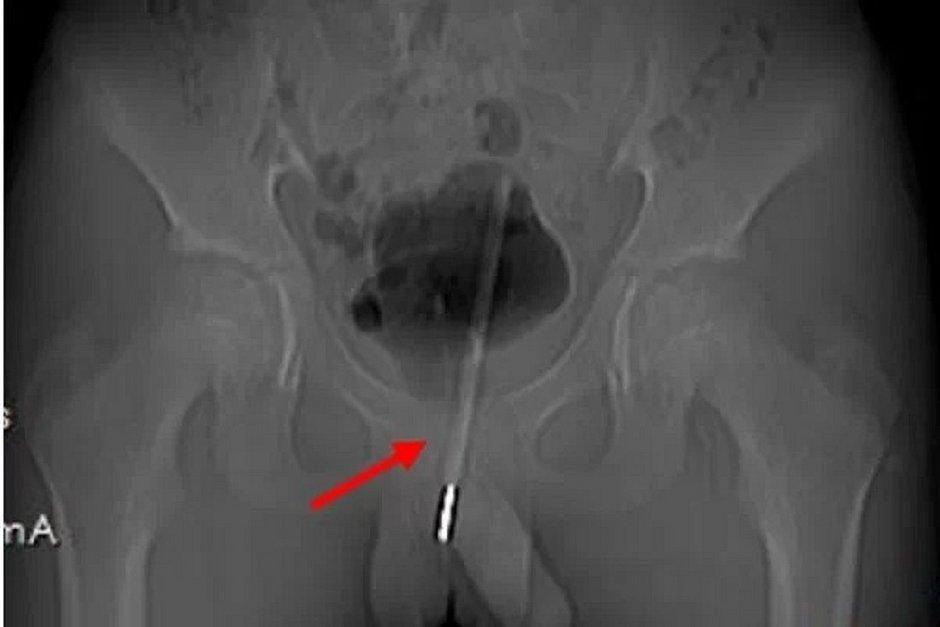

Exames de raio-X mostraram que o termômetro chegou à bexiga do menino. Os médicos temiam que ele pudesse machucar outros órgãos se fosse retirado da mesma forma que entrou e optaram por uma cirurgia menos invasiva, com pequenas incisões, para retirá-lo pela bexiga. A operação foi bem-sucedida e sem sequelas para o paciente.